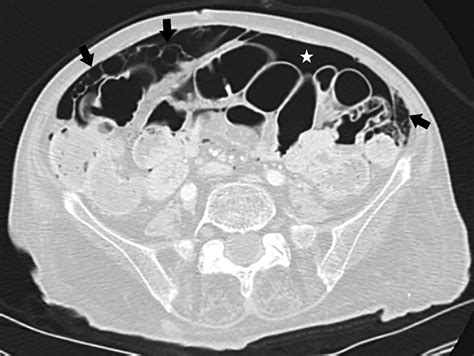

CT Scan The gold standard; provides detailed visualization of gas cysts.

When reviewing imaging, radiologists look for the specific appearance of "bubbly" gas collections along the serosal or submucosal surfaces. Differentiating these cysts from free air (pneumoperitoneum) is the most critical step for the radiologist to ensure the patient is not facing a surgical emergency.